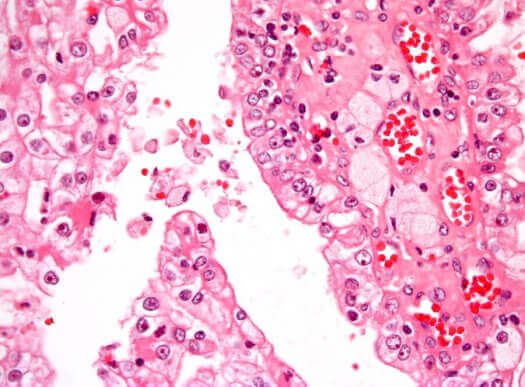

Kanker treedt op wanneer kwaadaardige cellen zich ongecontroleerd in het lichaam vermenigvuldigen. Het meest voorkomende type nierkanker bij kinderen wordt Wilms tumor of nefroblastoom genoemd. Het is solide en vormt zich in het onvolgroeide nierweefsel.